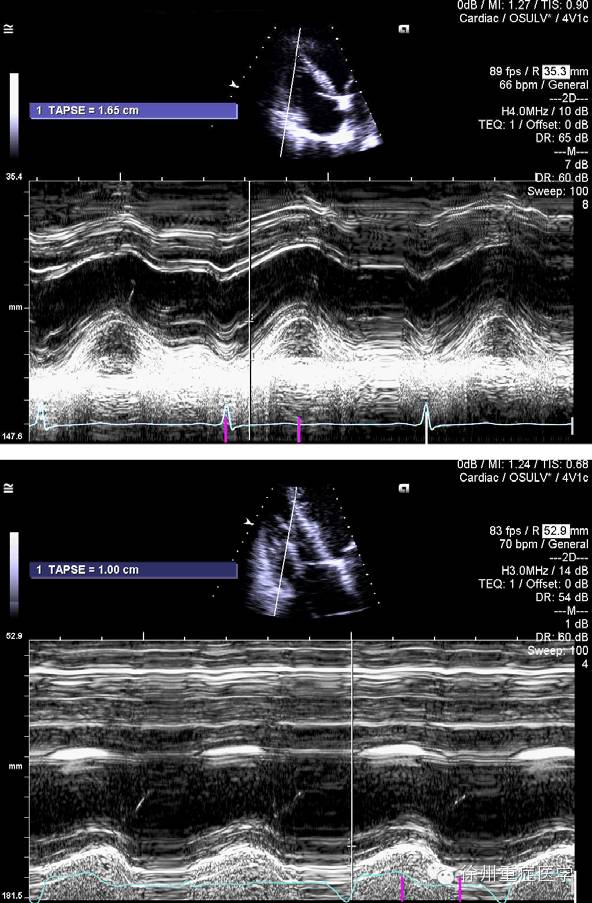

超声心动图和心衰(Ⅱ) 勿忘右心 那惊鸿的一瞥

m型超声心动图